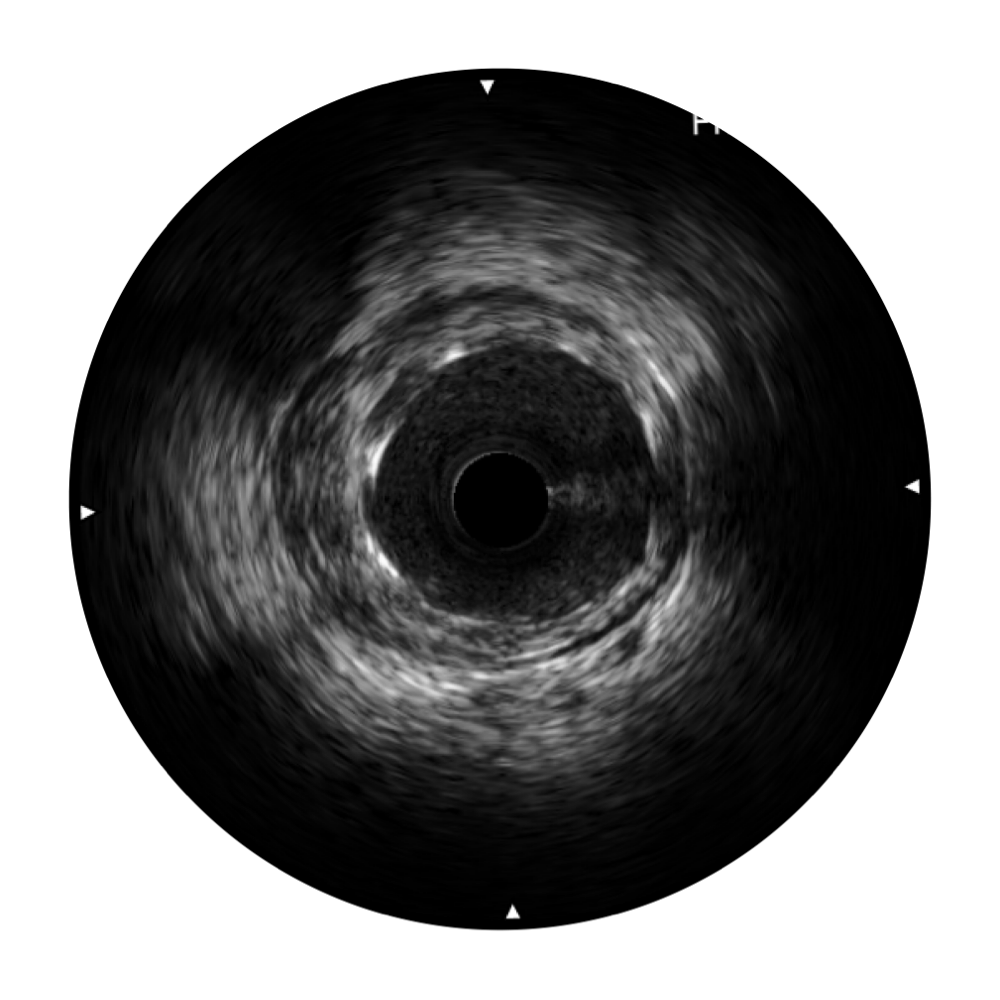

1.SonoSound® Crystal导管 米兰官方网站宽频IVUS图像

米兰官方网站宽频IVUS图像

传统IVUS图像

传统IVUS图像

对比传统IVUS导管成像,米兰官方网站宽频IVUS图像的近场支架梁显影更细腻,远场中膜外血管仍清晰可辨,兼顾远中近,兼顾分辨力与穿透深度